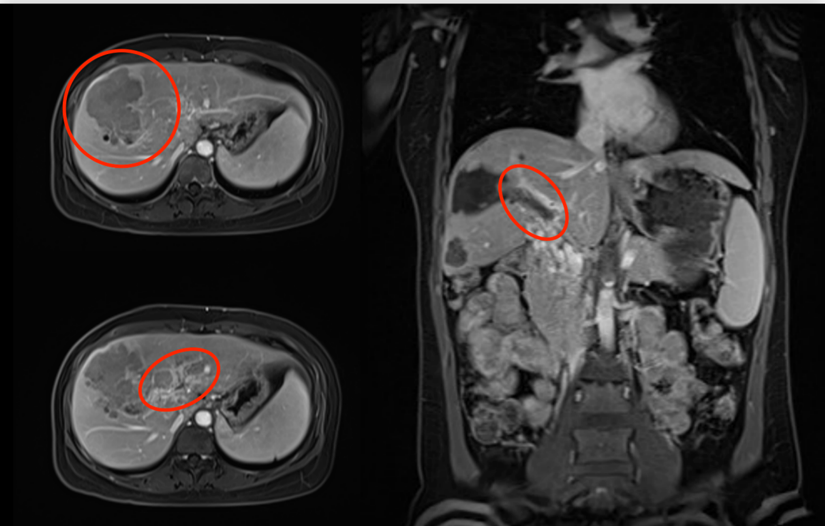

▲影像检查

考虑到刘女士的病情,团队为她实施了“三联疗法”,即通过介入化疗、仑伐替尼和PD-1抑制剂的三联治疗方案,为患者赢得手术根治机会。令人惊喜的是,在近4个月的“三联疗法”治疗后,患者复查磁共振发现肝脏肿瘤和门静脉癌栓完全坏死,肿瘤标志物指标也降到正常范围。

▲“三联疗法”治疗后影像及肿瘤指标情况